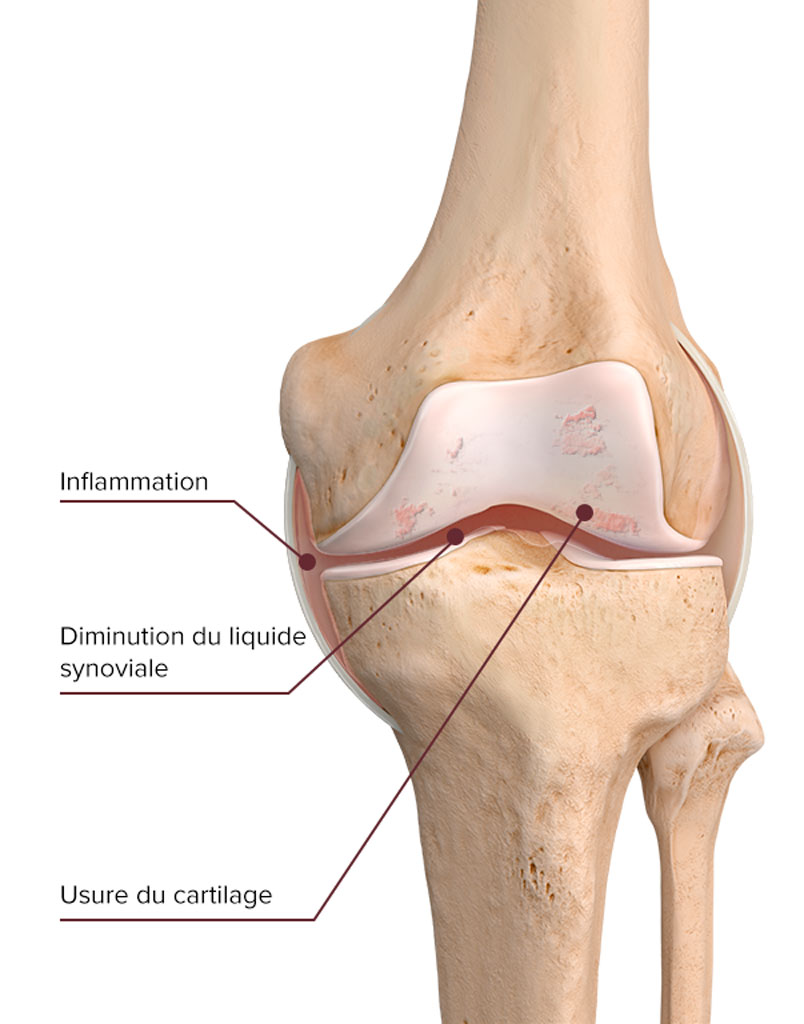

L’arthrose du genou, ou gonarthrose, est principalement due à une détérioration du cartilage articulaire et à une altération des propriétés viscoélastiques du liquide synovial. En effet, l’acide hyaluronique, principal composant du liquide synovial, est dégradé. Le liquide synovial ne lubrifie plus le cartilage et n’absorbe plus aussi efficacement les chocs et les contraintes mécaniques infligées à l’articulation lors d’un effort. C’est alors que la douleur se fait sentir.

Inflammation articulaire

Conséquences de la gonarthrose

- Activité physique limitée

- Tiraillement désagréable dans l’articulation

- Raideur matinale

- Inconfort en début de marche qui s’atténue après quelques pas

- Douleur au repos qui peut se transformer en douleur persistante